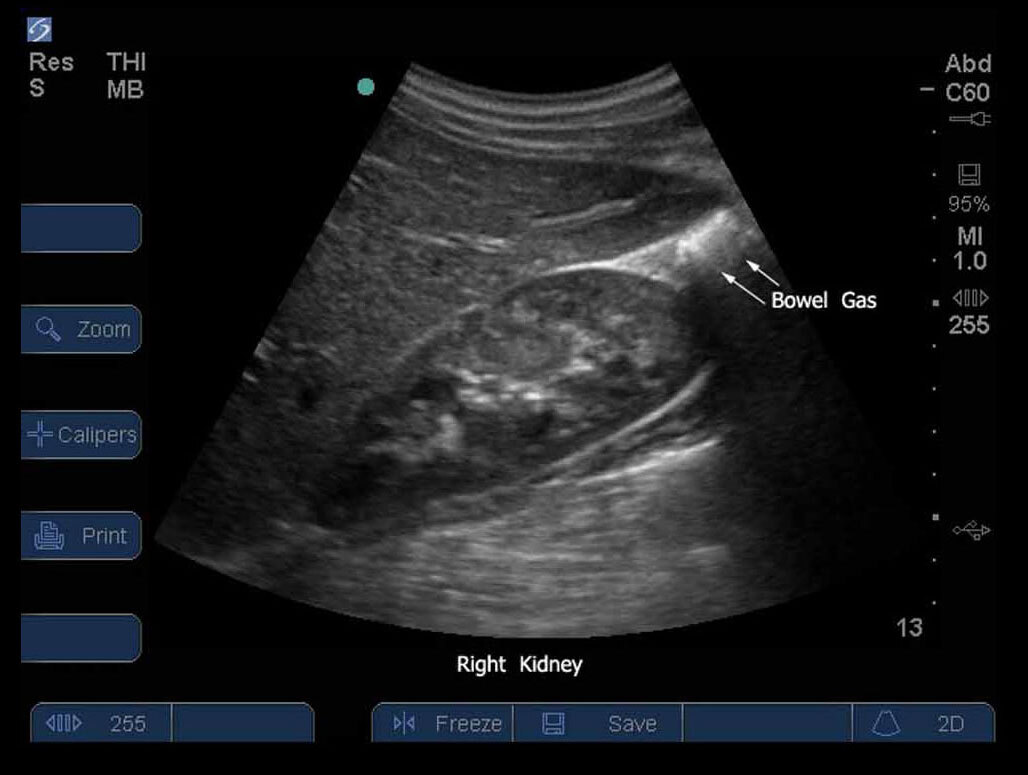

FAST Right Upper Quadrant (RUQ) 4 Image

S Series.